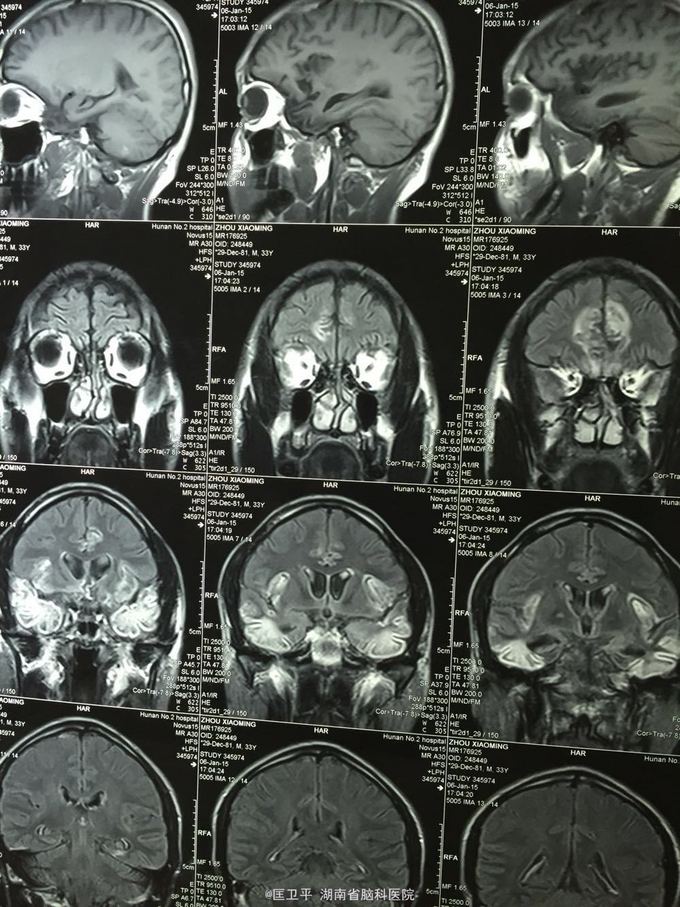

电击伤后智力低下,伤人毁物1年。 一年前在工地被电击伤昏迷,心跳呼吸停止,十几分钟后才有不规范的人工呼吸,持续约40分钟,心跳呼吸恢复。但患者智力低下,远近记忆很差,疑人害,伤人毁物严重,无法管理。

神清欠合作,五官无畸形,四肢活动正常,无神经定位体征。智能记忆很差,有被害妄想,有冲动攻击行为,无自知力,个人生活无法自理。